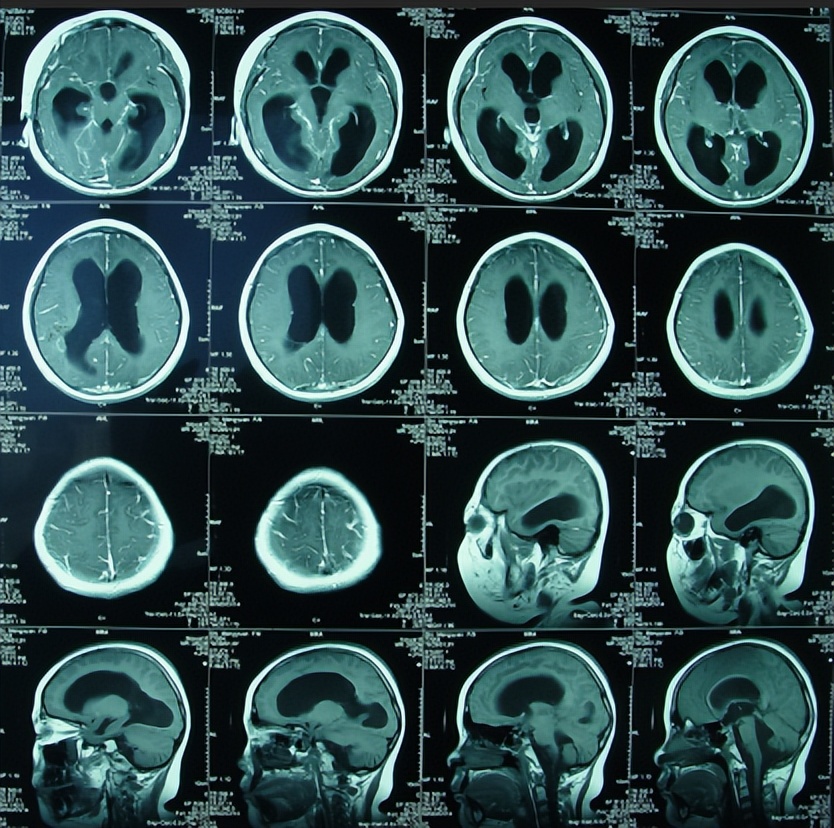

在2010年6月10日转入第3家医院给予结核性脑膜炎的治疗,在1周后即在2010年6月18日进行了脑CT的检查(图-3)示脑室进一步扩大,“因侧脑室旁的2个病灶的显示,证实了结核性脑膜炎的诊断”。

图-3:2010年6月18日头颅CT

脑CT检查后的当天,因头痛持续加重再次癫痫发作(自入该院后经常发生癫痫发作),测颅内压500mmH2O,于是进行了右侧脑室额角引流术。引流术后头痛迅速减轻,脑室引流共持续了2周,后因引流管脱出脑室而被迫停止引流。